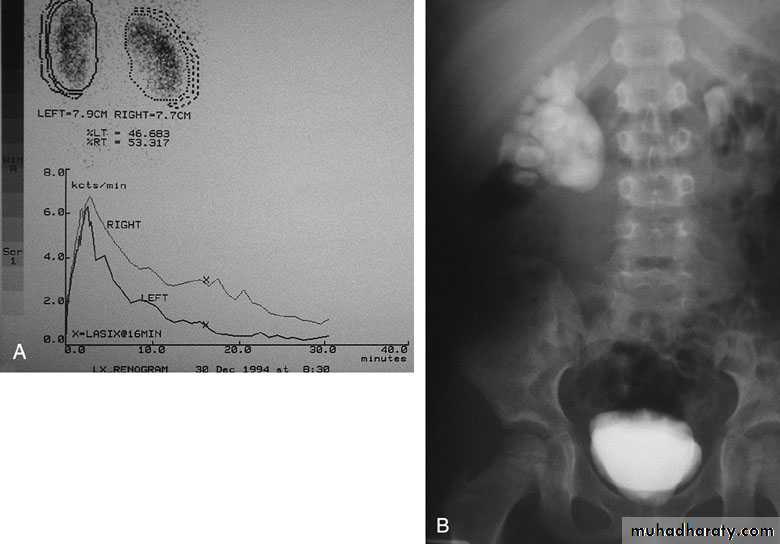

DIAGNOSIS

U/S: hydronephrosis

IVU: diagnostic , hydronephrosis with

fixed stenotic segment or complete

obstruction

CT scan: hydronephrosis that ends

abruptly

Magnetic Resonance Imaging

Radionuclide Renography: to see the

split function of each kidney

Pressure-Flow Studies: Whitaker test